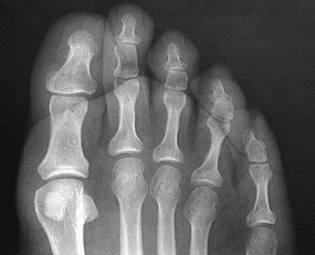

Radiographs may be obtained by directing the central ray perpendicular to the plane of the IR or by angling the central ray 10 degrees posteriorly. When a 10-degree posterior angle is used, the central ray is perpendicular to the metatarsals, reducing foreshortening. The TMT joint spaces of the midfoot are also better shown (Figs. 6-39 and 6-40).

Structures shown: The resulting image shows an AP (dorsoplantar) projection of the tarsals anterior to the talus, metatarsals, and phalanges (Figs. 6-43 to 6-45). This projection is used for localizing foreign bodies, determining the location of fragments in fractures of the metatarsals and anterior tarsals, and performing general surveys of the bones of the foot.

NOTE: The medial oblique is preferred over the lateral oblique because the plane through the metatarsals is more parallel to the IR, and it opens the lateral side joints of the midfoot and hindfoot better.

• Place the IR under the patient’s foot, parallel with its long axis, and center it to the midline of the foot at the level of the base of the third metatarsal.

• Rotate the patient’s leg medially until the plantar surface of the foot forms an angle of 30 degrees to the plane of the IR (Fig. 6-46). If the angle of the foot is increased more than 30 degrees, the lateral cuneiform tends to be thrown over the other cuneiforms.1

Structures shown: The resulting image shows the interspaces between the following: the cuboid and the calcaneus, the cuboid and the fourth and fifth metatarsals, the cuboid and the lateral cuneiform, and the talus and the navicular bone. The cuboid is shown in profile. The sinus tarsi is also well shown (Fig. 6-47).

• Rotate the leg laterally until the plantar surface of the foot forms an angle of 30 degrees to the IR.

• Support the elevated side of the foot on a 30-degree foam wedge to ensure consistent results (Fig. 6-48).

Structures shown: The resulting image shows the interspaces between the first and second metatarsals and between the medial and intermediate cuneiforms (Fig. 6-49).